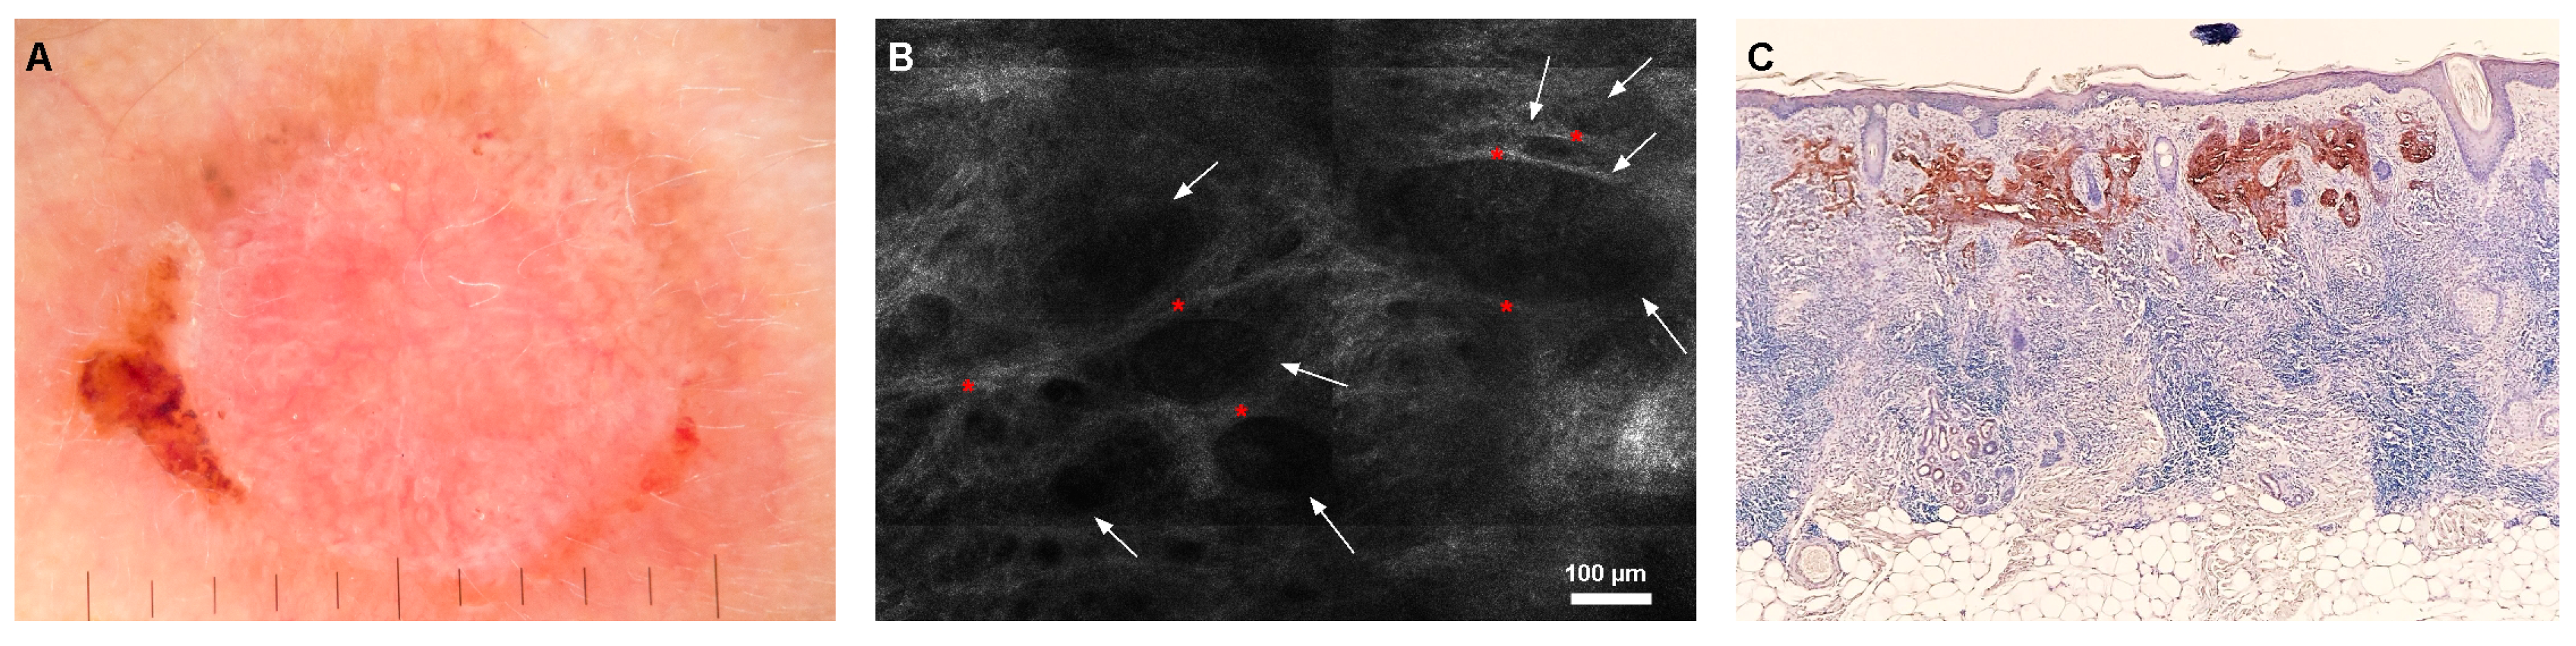

- Ghita, M.A.; Caruntu, C.; Rosca, A.E.; Kaleshi, H.; Caruntu, A.; Moraru, L.; Docea, A.O.; Zurac, S.; Boda, D.; Neagu, M. Reflectance confocal microscopy and dermoscopy for in vivo, non-invasive skin imaging of superficial basal cell carcinoma. Oncol. Lett. 2016, 11, 3019–3024. [Google Scholar] [CrossRef] [PubMed]

- Peppelman, M.; Wolberink, E.A.W.; Blokx, W.A.M.; van de Kerkhof, P.C.M.; van Erp, P.E.J.; Gerritsen, M.-J.P. In vivo diagnosis of basal cell carcinoma subtype by reflectance confocal microscopy. Dermatology 2013, 227, 255–262. [Google Scholar] [CrossRef]

- Borsari, S.; Pampena, R.; Lallas, A.; Kyrgidis, A.; Moscarella, E.; Benati, E.; Raucci, M.; Pellacani, G.; Zalaudek, I.; Argenziano, G.; et al. Clinical indications for use of reflectance confocal microscopy for skin cancer diagnosis. JAMA Dermatol. 2016, 152, 1093–1098. [Google Scholar] [CrossRef] [PubMed]